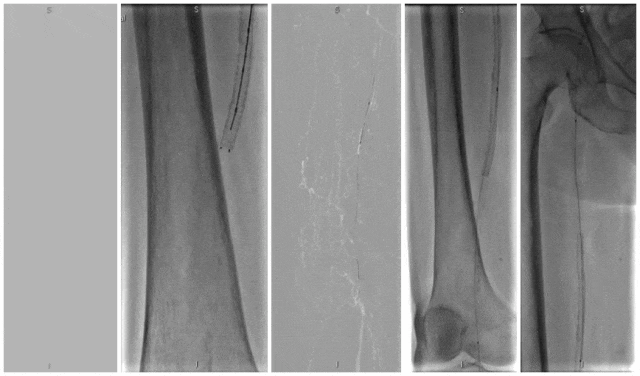

膝下动脉病变的激光治疗

★ 膝下动脉病变特点

★ Turbo Elite导管应用经验

使用2.0mm Turbo Elite导管治疗膝下动脉病变的技术要点:

缓慢推进导管(<1mm/秒)

能量参数个性化设置

联合球囊扩张优化效果

图:术前

图:4mm和3mm球囊扩张腘和胫后动脉

图:术后

★ 临床研究数据

单中心回顾性研究(2019年7月至2020年6月)纳入29例患者:

技术成功率:96.6%(28/29)

并发症发生率:6.9%

6个月靶血管通畅率:87.6%

6个月免于截肢生存率:93.1%